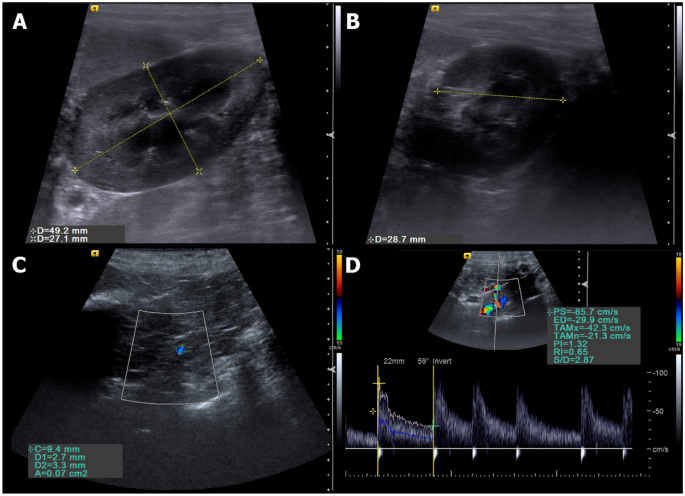

All patients evaluated by B-mode ultrasound showed kidney size and architecture within normal parameters, with homogeneous and hypoechoic aspect compared to splenic parenchyma, and preserved corticomedullary ratio, although a discrete loss of cortical thickness was detected in some patients (Fig. 1). Only the renal artery area was increased (P = 0.0003) in CG during 4th month and in TG during 1st to 6th months. The others analysed parameters were similar between groups (Tables 1, 2 and 3).

Ultrasonographic evaluations performed. (A) B mode sonographic sagittal view of the left kidney of a bitch delimited by the electronic callipers, measuring the length and height. (B) B mode sonographic transverse view of the left kidney of a bitch at the level of the renal hilum to measure the transverse height. (C) Color Doppler sonographic image of the renal artery (delimitated by the circle calliper) to obtain the vessel area. (D) Pulsed-wave Doppler of the renal artery to obtain the spectral tracing and Doppler flowmetry indices.